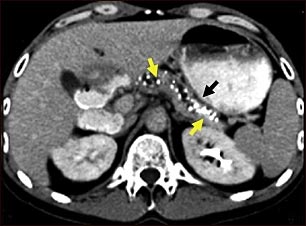

Tomografía computarizada de una pancreatitis crónica

TC del abdomen superior que muestra múltiples calcificaciones blancas. Éstas se presentan en la pancreatitits crónica.